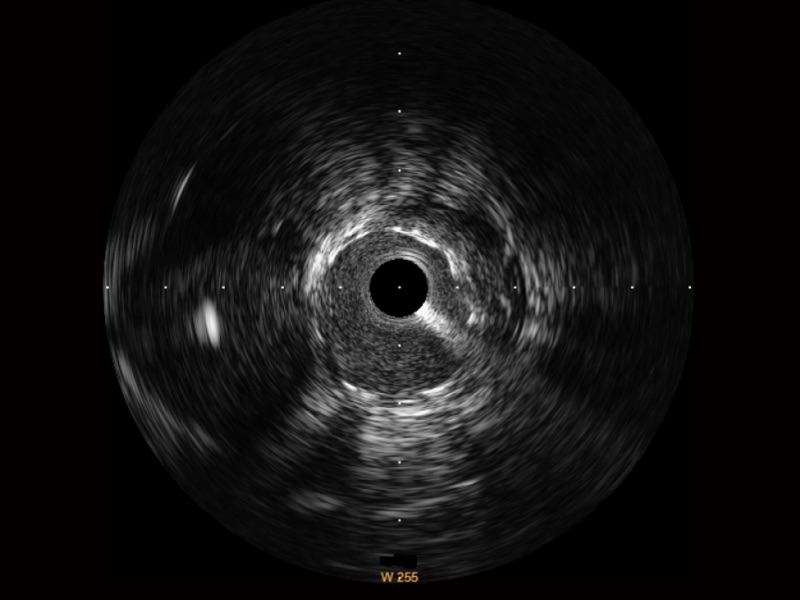

亚星官网宽频IVUS图像

传统IVUS图像

对比传统IVUS导管成像,亚星官网宽频IVUS图像的近场支架梁显影更细腻,远场中膜外血管仍清晰可辨,兼顾远中近,兼顾分辨力与穿透深度